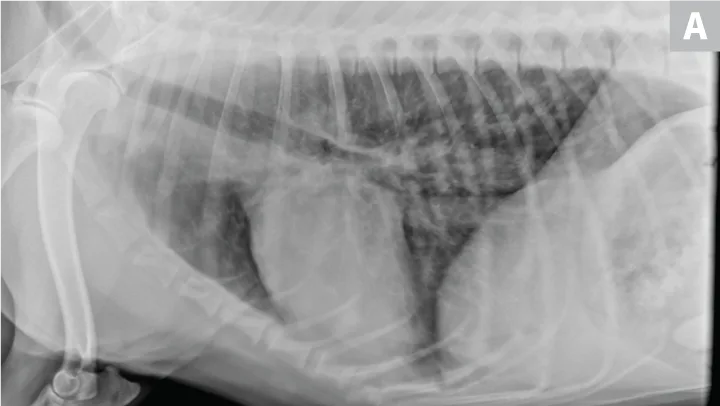

Nonspecific illness and respiratory signs may be appreciated. Leukocytosis, left shift, and pyrexia may be present.34 Radiographs often reveal an alveolar pattern, trapped gas (vesiculated), and/or pleural effusion. Bronchial malpositioning is uncommon (Figure 6).35 Confirmation via ultrasonography, bronchoscopy, and/or CT is recommended.36,37 Pleural fluid varies widely in gross and cytologic appearance. Although nonspecific, the presence of pleural fluid, alveolar disease, and acute respiratory signs is suggestive. Immediate lung lobectomy is warranted.

FIGURE 6

Lung lobe torsion. Note classic vesicular pattern associated with gas trapping and pleural effusion. Bronchial attenuation or displacement is subtle and often absent.